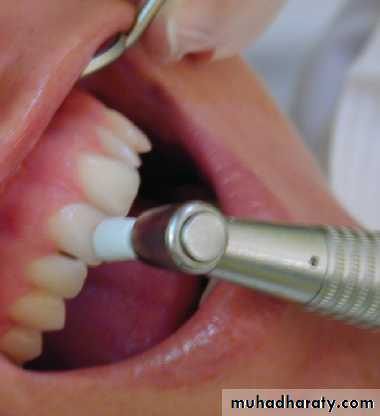

1. Hot air 2. Hot water 3. A hot burnisher 4. Hot gutta-percha 5. Hot compound 6. Polishing of crown with a rubber cupThermal test